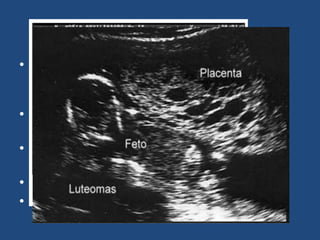

Etiología ecográfica

• Múltiples áreas hipoecoicas que corresponden

a las vellosidades hidrópicas con un patrón en

tormenta de nieve.

• No hay saco gestacional normal o de un feto.

• En la mola hidatiforme parcial se observa

áreas focales de cambios trofoblásticos y de

tejido fetal.

Mola Parcial

• Presenta características de una placenta de

desarrollo normal y de una mola hidatiforme

completa.

• Gama de vellosidades desde normales a

quísticas.

• La hiperplasia del trofoblasto es focal o en

parches.

• Afecta al sincitiotrofoblasto.

• Puede estar presente el feto.